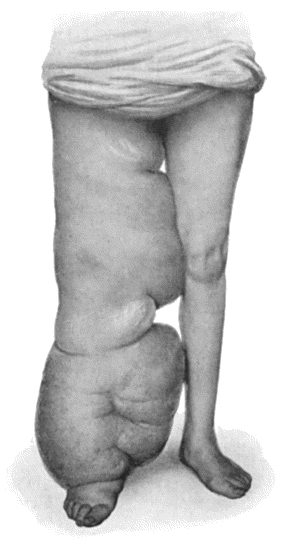

Another modification is to raise the flap but leave it connected at both ends like the piers of a bridge; this method is well suited to defects of skin on the dorsum of the fingers, hand and forearm, the bridge of skin is raised from the abdominal wall and the hand is passed beneath it and securely fixed in position; after an interval of 14 to 21 days, when the flap is assured of its blood supply, the piers of the bridge are divided (Fig. 1). With undermining it is usually easy to bring the edges of the gap in the abdominal wall together, even in children; the skin flap on the dorsum of the hand appears rather thick and prominent—almost like the pad of a boxing-glove—for some time, but the restoration of function in the capacity to flex the fingers is gratifying in the extreme.

Fig. 1.—Ulcer of back of Hand covered by flap of skin raised from anterior abdominal wall. The lateral edges of the flap are divided after the graft has adhered.